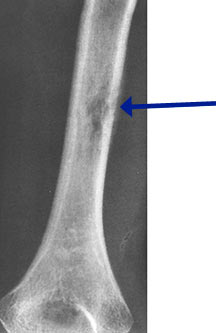

- May arise from any bone and any site within a bone (epiphyseal, metaphyseal, diaphyseal)

- Radiographically variable appearance: may appear benign (geographic) or malignant (permeative or moth eaten)

- Femur

- Humerus

Radiographic Presentation